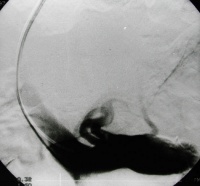

造影显示门静脉高压